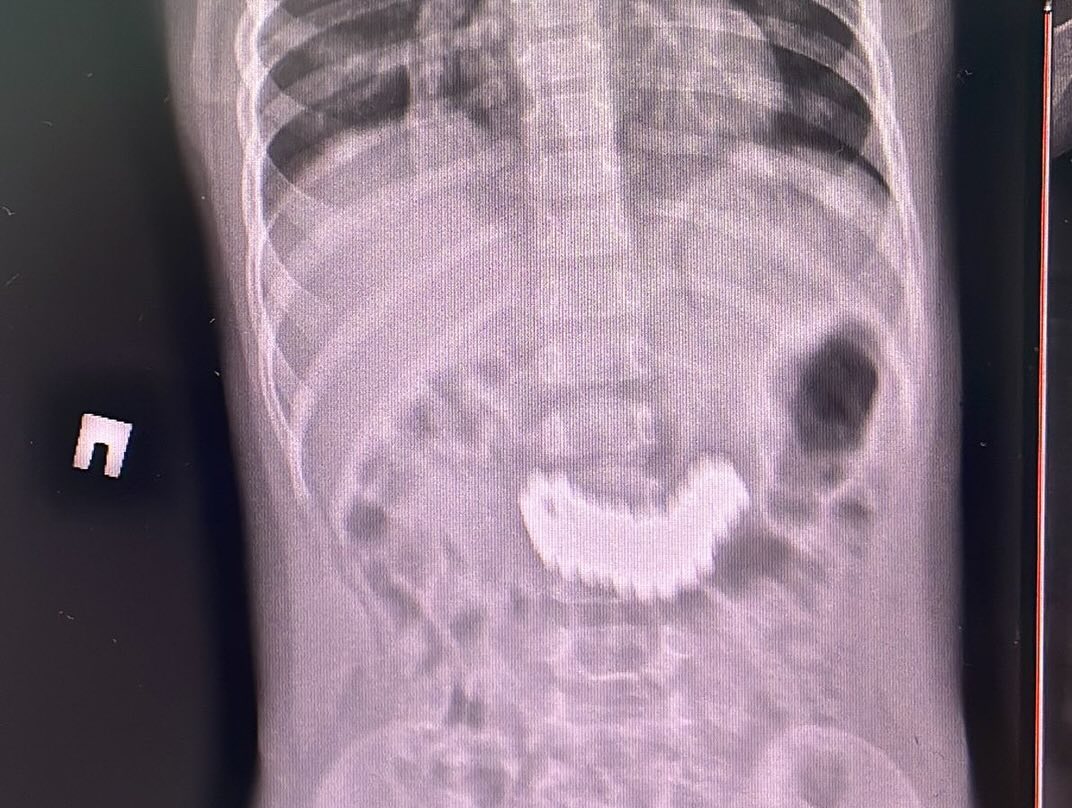

Как отметили в ЦДНМП, при проведении рентгенографии органов брюшной полости были выявлены металлические предметы размером 6,2 × 2,2 см. Ребенка экстренно госпитализировали для удаления инородного тела.

Первоначально специалисты попытались извлечь предметы эндоскопическим путем, однако из-за плотного скопления магнитов это оказалось невозможно. Было принято решение о проведении хирургического вмешательства – лапаротомии и гастротомии. В ходе операции из желудка ребенка извлекли 105 магнитных бусин.